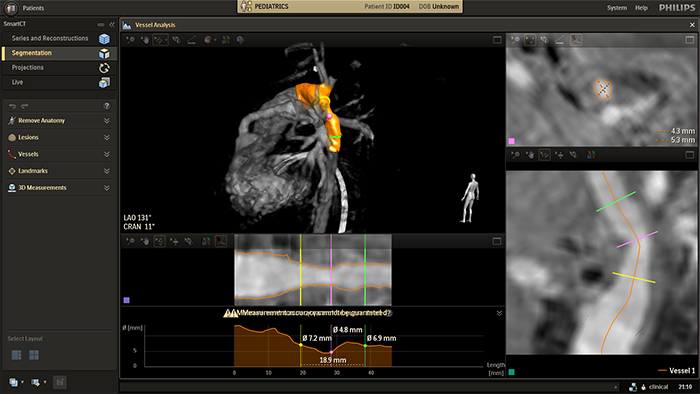

Discover SmartCT, the next leap in simplifying and advancing in-room 3D imaging for congenital heart disease

The Philips image-guided therapy clinical application software SmartCT allows any clinical user to perform 3D imaging regardless of their level of experience with 3D imaging*. Via the touch screen at the table, you can access clinically tailored 3D acquisition protocols and advanced visualization and measurement tools that depict the type and extent of disease with great detail. *The user level of expertise required is described in the Instructions for Use as the Intended Operator Profile.

Automatic vessel analysis from rotational angiography with SmartCT